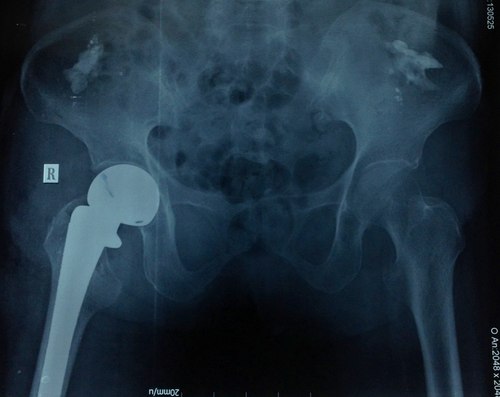

H́nh ảnh phim chụp khớp háng bệnh nhân 93 tuổi. Ảnh: T. Đ.P

Bác sĩ Phú cho biết, bệnh nhân được nhanh chóng phẫu thuật thay khớp háng chuôi dài thế hệ mới. Đây là loại khớp háng mới được ứng dụng cho các loại găy cổ xương đùi phức tạp có đường găy lan xuống dưới làm mất vững. Sau hậu phẫu 7 ngày, bệnh nhân đă vận động nhẹ tại giường chân phải và bớt đau đớn. Khả năng sau 3 ngày nữa là bệnh nhân có thể xuất viện.